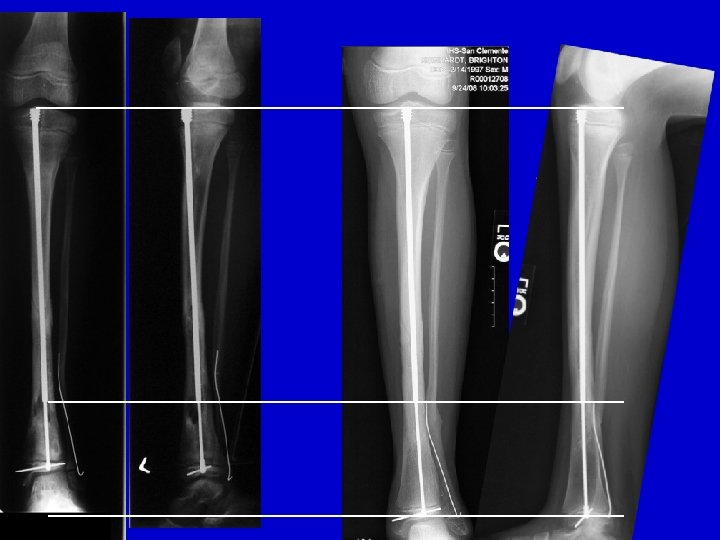

Type I Treatment Lateral AP

preop postop

Flexible IM nail 3 year follow-up

Fassier-Duval Telescopic Nail

LLD